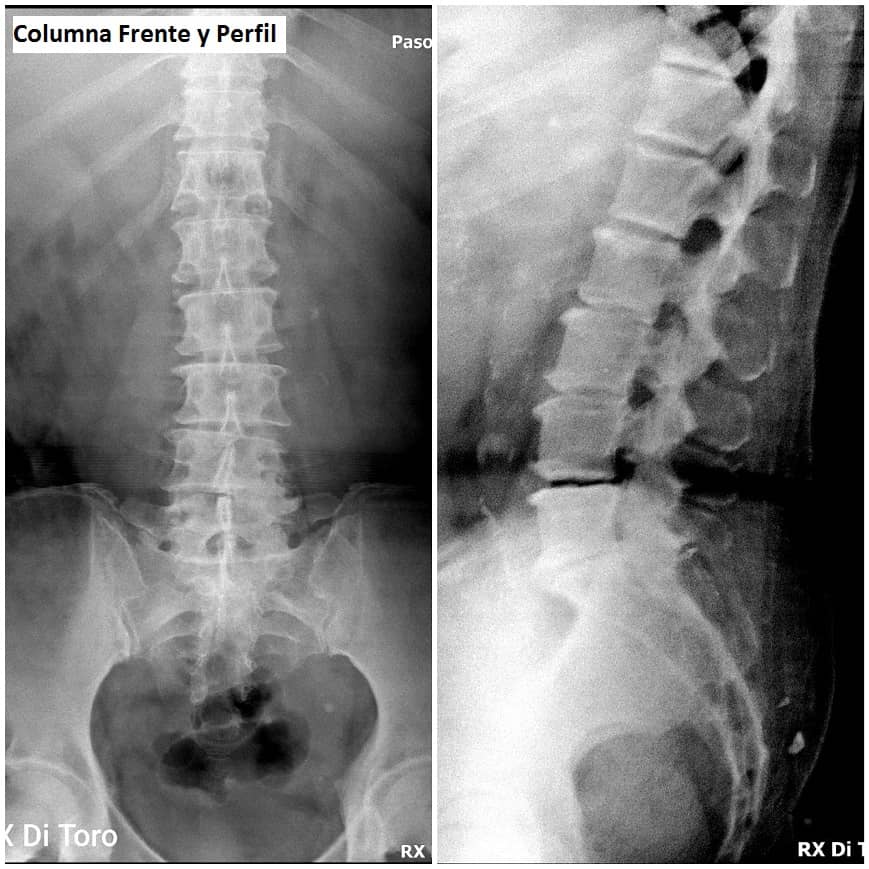

Utilizamos sensores Flat Panel, que nos permiten acortar al Máximo el tiempo de exposición (Dosis de Radiación) y obtener la adquisición inmediata de las imágenes.